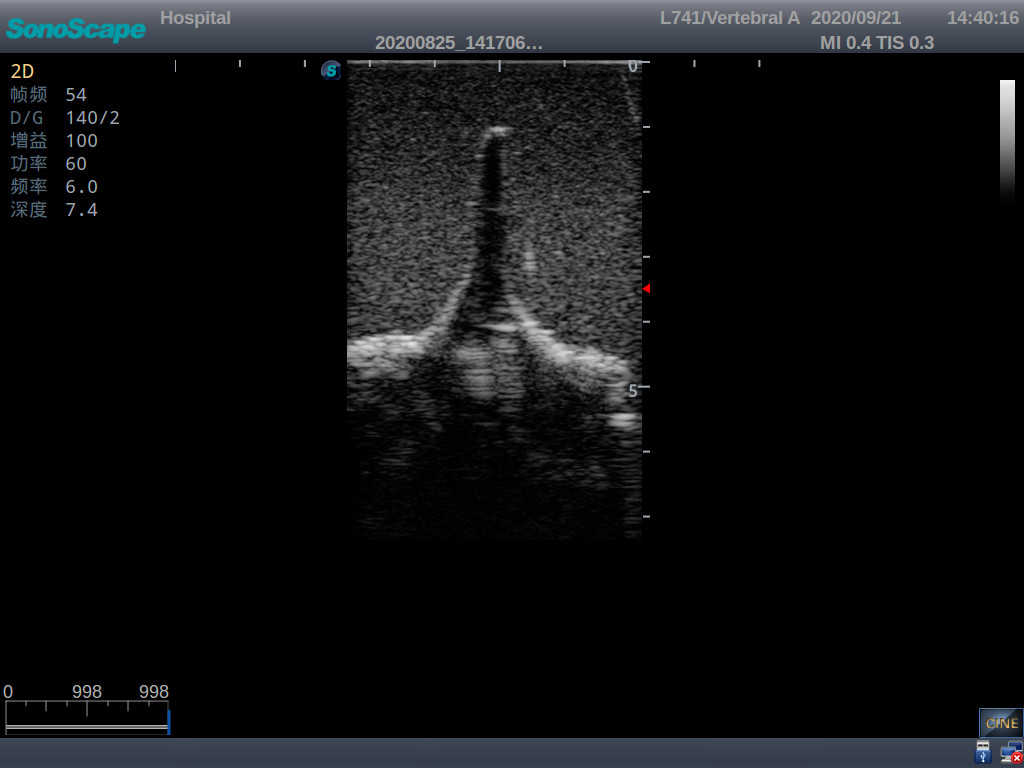

Model TYE1549.2

This model is an ideal choice for ultrasound-guided adult lumbar puncture training with true-to-life skin feel and touch, accurate anatomical structures as well as real clinical ultrasound images. Realistic resistance to needle tips and correct landmarks provide excellent hands-on experience.

Accurate anatomical structure of L1-L5 and the vertebral canal

2)  Real clinical ultrasound images